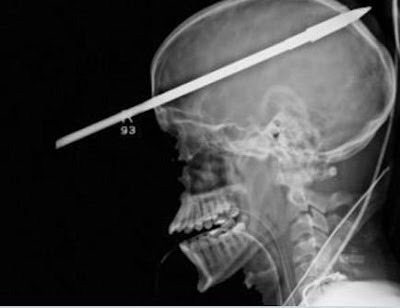

In June 2012, 16-year-old Florida resident Yasser Lopez was on a fishing trip when a friend accidentally shot him with a three-foot fishing spear while loading the speargun. Upon Lopez’s admission to hospital, the injuries looked severe. The spear had hit him just above his right eye, passed through his skull and brain, and exited the back of his head.